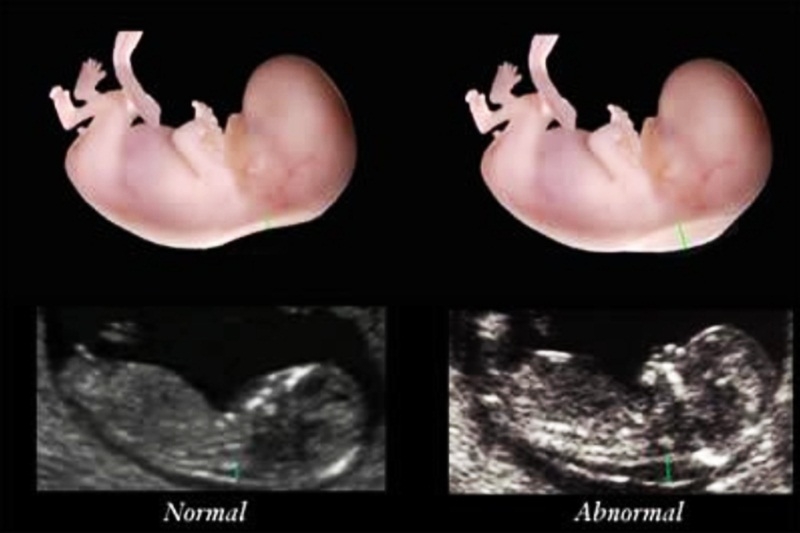

Độ mờ da gáy là hình ảnh siêu âm về sự tích tụ chất lỏng dưới da phía sau cổ của thai nhi trong ba tháng đầu thai kỳ và xuất hiện dưới dạng hình ảnh màu đen hoặc có mây trên màn hình. Thai nhi có bất thường nhiễm sắc thể, dị tật tim và một số hội chứng di truyền làm tăng độ mờ da gáy.

Độ mờ da gáy là một phần của xét nghiệm sàng lọc Độ mờ da gáy là hình ảnh về sự tích tụ chất lỏng dưới da phía sau cổ

Trước hết, bạn phải hiểu rằng chất trong ở cổ là một chất lỏng tích tụ ở phía sau cổ của thai nhi. Các bác sĩ sử dụng độ mờ da gáy để đánh giá xem thai nhi có nguy cơ mắc hội chứng Down hay các dị tật bẩm sinh khác hay không. Những thai nhi bất thường có nhiều chất lỏng dưới da ở sau cổ hơn những thai nhi khỏe mạnh.

Siêu âm đo độ mờ da gáy rất quan trọng Các bác sĩ sản khoa đo độ mờ da gáy bằng siêu âm